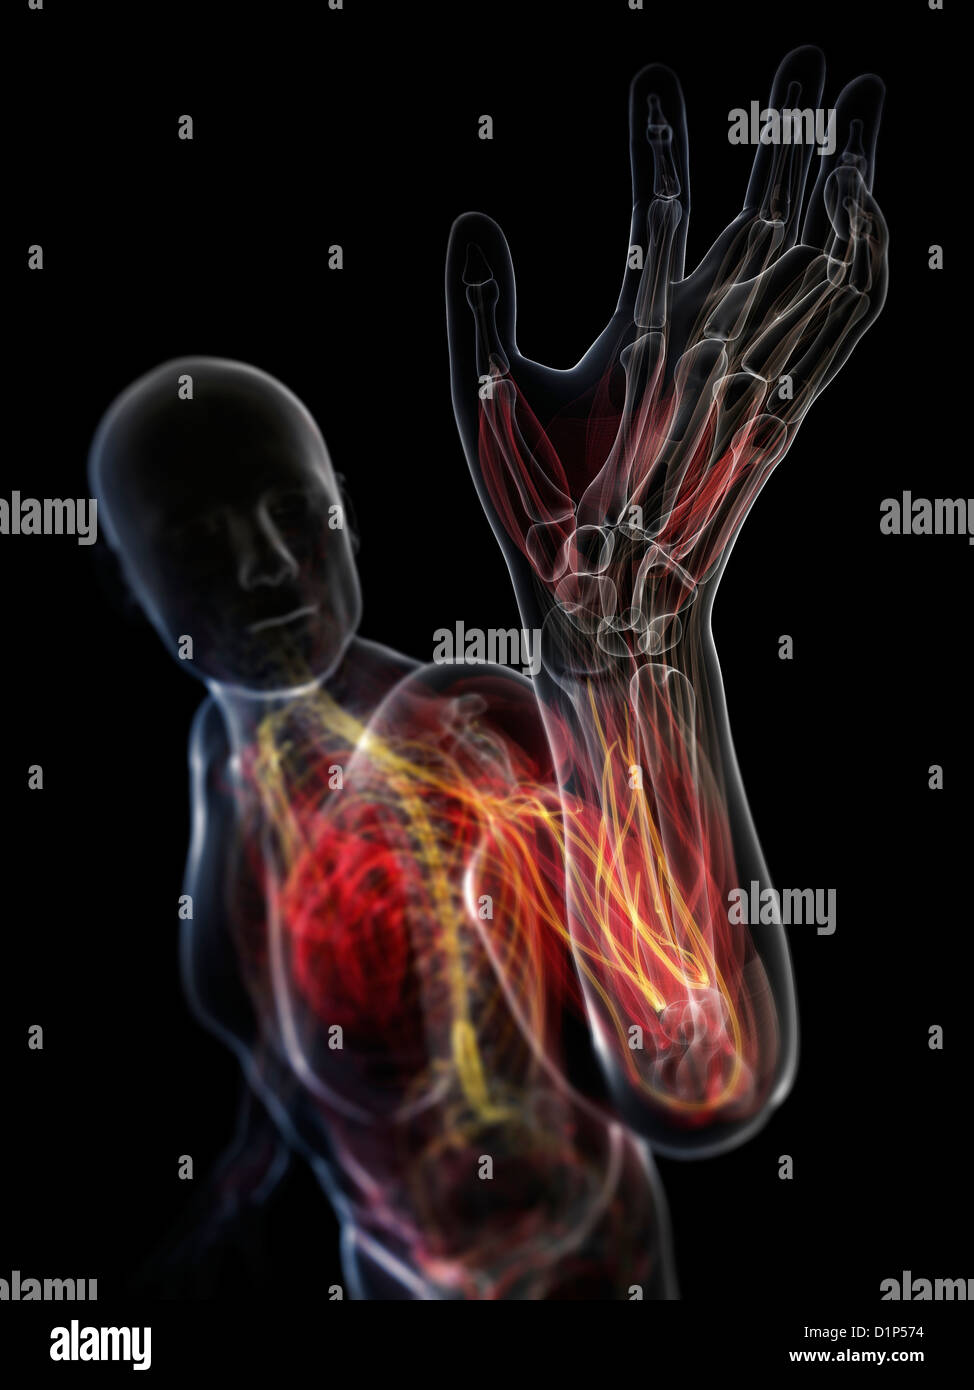

RFWW2CNW–Die männliche Anatomie, Gliedmaßen und hip Muskel- und Skeletterkrankungen Systeme, mit interner Muskelschichten. Vorder- und Rückansicht. schwarzen Hintergrund. 3d-Abbildung.